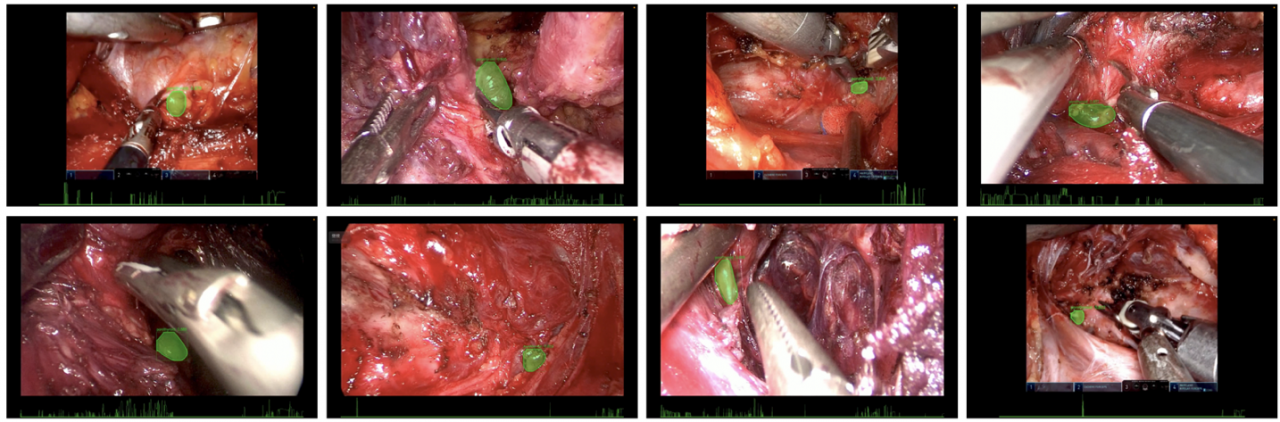

SmartThyroid系统术中实时识别甲状旁腺的可视化效果图

该研究聚焦学科远程入路腔镜及机器人甲状腺手术中甲状旁腺保护这一国际公认难题,开发了人工智能系统“SmartThyroid”。在最终测试中,该系统表现出卓越性能:其识别效率显著高于所有外科医生,可在1秒内迅速识别并持续追踪手术视频中出现的关键结构——甲状旁腺,相比于低年资外科医生,其旁腺识别准确率更高、持续时间更长。值得特别指出的是,在AI辅助下,低年资外科医生的旁腺识别准确率获得了显著提高,同时所有外科医生的识别效率与稳定性也得到了明显改善。研究结果表明,“SmartThyroid”能够在复杂甲状腺手术场景中提供实时、精准的术中辅助,不仅可有效提高手术安全性,降低相关并发症风险,还为甲状旁腺保护与手术导航提供了切实可行的解决方案,具有重要的临床推广价值。